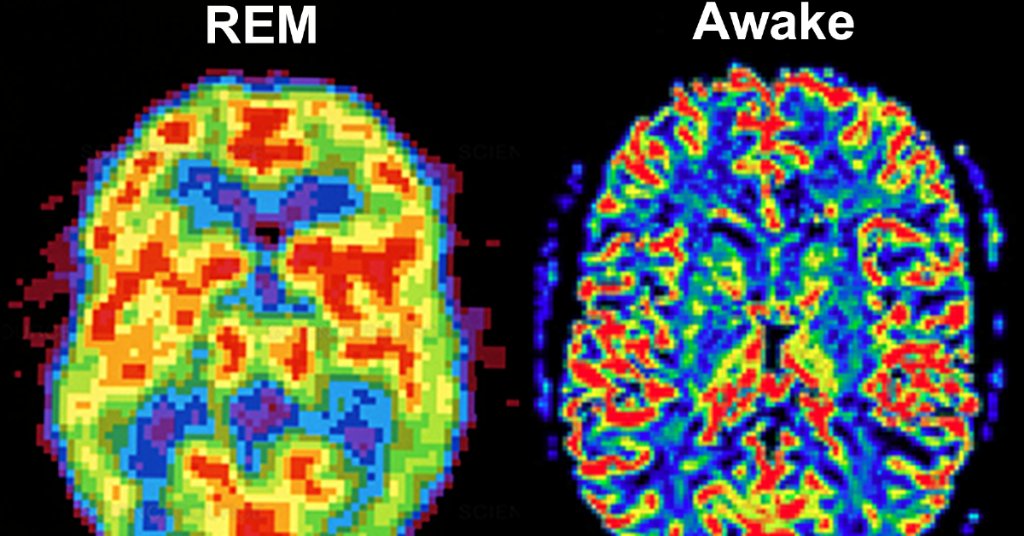

image

Слева быстрая фаза сна, справа бодрствующий мозг